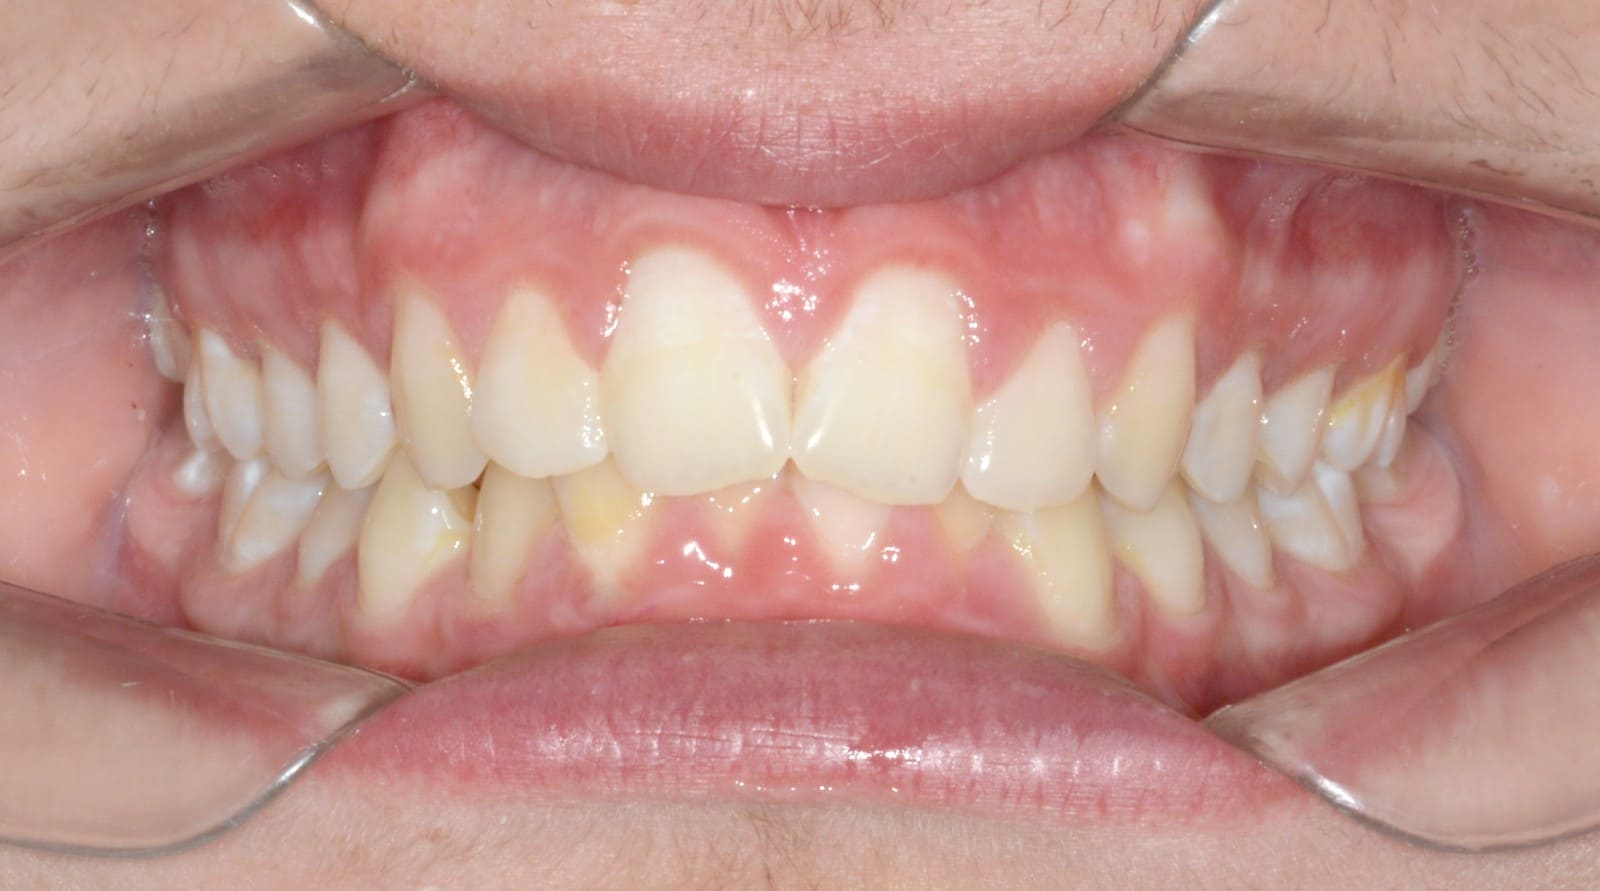

Invisalign Teen Conditions – Class II div 1 – Deep bite – Increased overjet – Narrow arches

Clinical Indications

- Class II div 1

- Deep bite

- Increased overjet

- Narrow arches

Initial